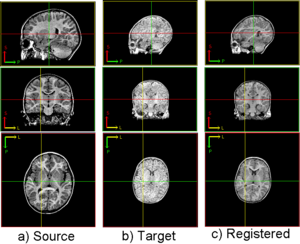

DRAMMS: 2D/3D deformable image registration